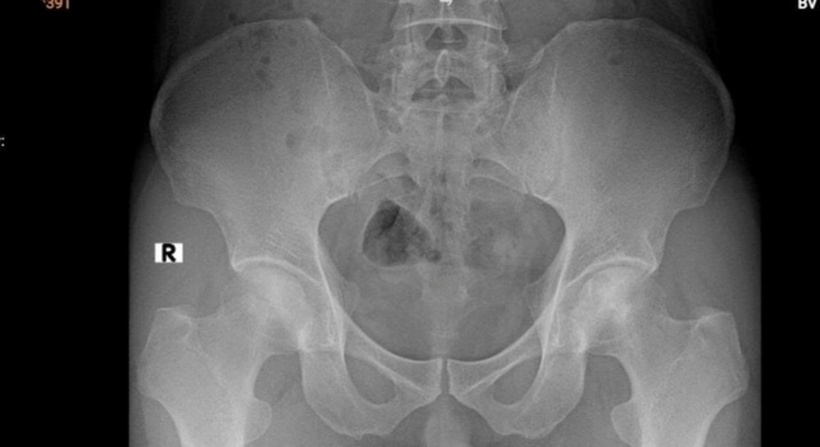

Bệnh nhân có dấu hiệu hoại tử vô mạch chỏm xương đùi hai bên độ 2 theo ficat và alert. Ảnh: Sức khoẻ & Đời sống.

Kết quả chụp MRI cho thấy phần chỏm xương cánh tay trái bị hoại tử, ổ hoại tử lan xuống vùng cổ và thân xương cánh tay. Khi chụp X-quang phần khớp háng nhận thấy dấu hiệu hoại tử vô mạch chỏm xương đùi hai bên độ 2 theo ficat và alert (tình trạng tế bào xương ở chỏm xương đùi chết đi do mất nguồn cung cấp máu).